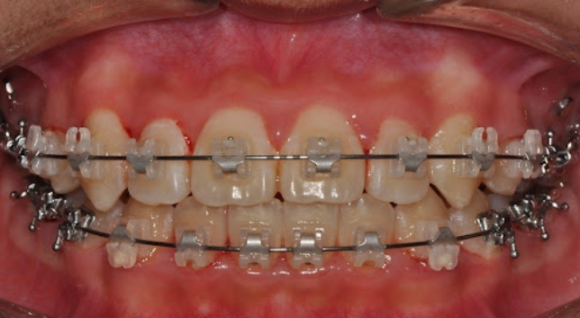

자가결찰 브라켓(교정 장치) 예시

세라믹 자가결찰 장치란 세라믹 재질로 만들어진 교정 장치의 한 종류입니다.

심미성: 금속 장치보다 눈에 덜 띄는 세라믹 소재 선택 가능

체어타임: 자가결찰 방식은 철사 조정 시간이 상대적으로 짧을 수 있음

치료 효과: 장치 종류보다 치료 계획과 개인 상태가 더 크게 작용